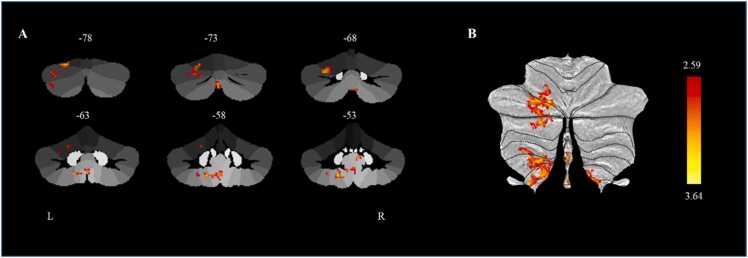

The results showed that a higher p factor at baseline was significantly associated with baseline increased connectivity between the left cerebellar lobule VIIb and several other regions, including left lobules VI (62 voxels), Crus I (103 voxels), Crus II (58 voxels), VIIIb (39 voxels) and IX (60 voxels) at baseline. Among these regions, the peak region was the left cerebellar lobule VI (MNI coordinate: x = −20, y = −78, z = −22), which belongs to the frontoparietal network (Fig. 3). The increased connectivity between the left cerebellar lobule VIIb and left cerebellar lobule VI at baseline predicted higher p factor at follow-up (β = 0.140, p < 0.05, 95% CI [0.028, 0.251]) after controlling for gender, age, site, parental education level, TIV, and the autoregressive p factor. The linear mixed model analysis also yielded consistent results with the present findings (For detailed information, see the Supplemental Results) Further analysis revealed that age (t = −0.054, p = 0.338), gender (t = −0.176, p = 0.119), site (t = 0.176, p = 0.170), and parental education level (t = 0.042, p = 0.485) did not significantly moderate the longitudinal prediction of connectivity between the left cerebellar lobule VIIb and left cerebellar lobule VI on the follow-up p factor.